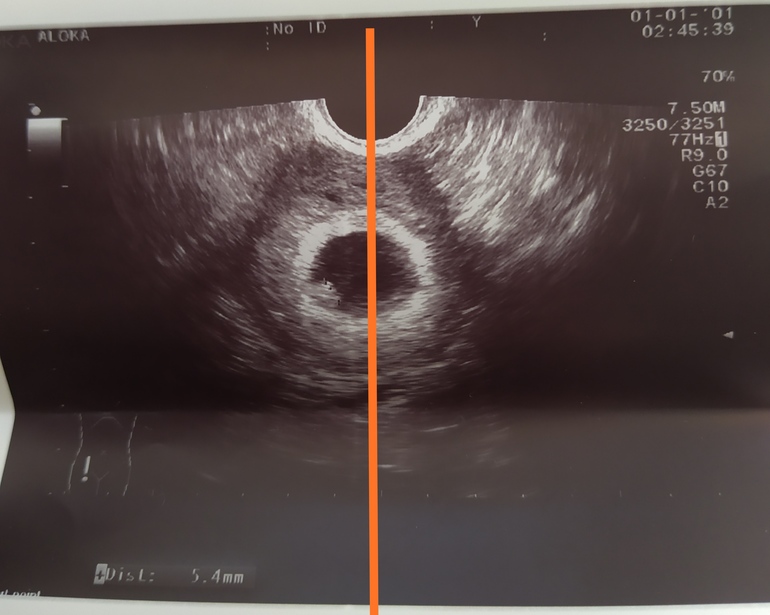

Вот моё узи с младшим сыном примерно на этом же сроке

По Рамзи смотрят на сроке 6-7 недель про прикреплению эмбриона,если УЗИ трансвагинально,то слева мальчик,а справа девочка,если по животу,то наооброт слева девочка,а справа - мальчик,вот для примера мое узи на сроке 6+2 УЗИ трансвагинально и у меня прикрепление слева,по нему у меня мальчик,но так и есть

А вот у меня где то посередине?)

Ну да почти по середине,но чуть левее мне кажется

Отличные новости🥰. По методу Рамзи девчуоя, если УЗИ было вагинаььное

Смотрят пол по прикрепления малыша

Ну видно малыша в по одном пузыре и он справа и плацента больше справа